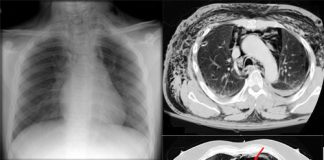

Pnömomediastinum

Pnömomediasten, mediastinal boşlukta hava bulunması ile karakterize nadir görülen ancak acil servislerde karşılaşılabilen önemli klinik durumlardan biridir. Travma, alveoler rüptür, astım atağı, yoğun öksürük,...